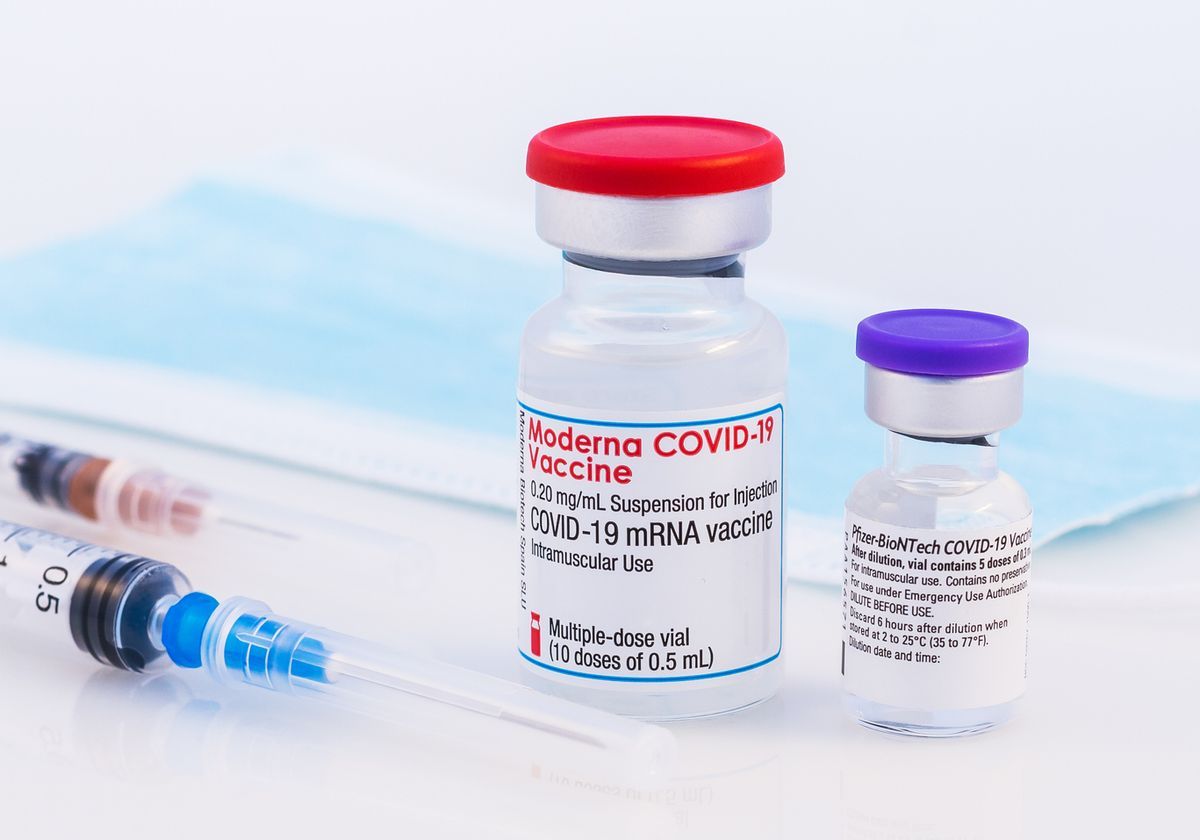

Η φαρμακοβιομηχανία Moderna Inc ανακοίνωσε σήμερα ότι απέσυρε 764.900 δόσεις του εμβολίου της για την Covid-19 δημιουργώντας εύλογες ανησυχίες για όσους έχουν εμβολιαστεί με το συγκεκριμένο εμβόλιο

Αρκεί να αναλογιστεί κανείς ότι τα εμβόλια της Moderna αποσύρονται την στιγμή που αποκαλύπτεται από την EudraVigilance, την ευρωπαϊκή βάση δεδομένων ότι μέχρι τις 26 Μαρτίου του 2022 είχαν καταγραφεί 42.507 θάνατοι και 3.984.978 παρενέργειες μετά τον εμβολιασμό κατά του κορωνοϊού.

Οι μισές περίπου παρενέργειες είναι σοβαρές, συγκεκριμένα οι 1.843.512, σύμφωνα με το Vaccineimpact.

Η Moderna αποφάσισε να αποσύρει τις συγκεκριμένες δόσεις αφού βρέθηκε ξένο σώμα μέσα σε φιαλίδιο που παρασκευάστηκε από την εταιρεία Rovi.

Οι δόσεις αυτές διανεμήθηκαν στη Νορβηγία, την Πολωνία, την Πορτογαλία, την Ισπανία και τη Σουηδία τον Ιανουάριο.

Συνεπώς κάποιος θα αναρωτηθεί ευλόγως κατά πόσο τα εμβόλια αυτά που έχουν ήδη χρησιμοποιηθεί σε ένα μεγάλο ποσοστό αποτελούν απειλή για την υγεία των εμβολιασμένων.

Πάντως για να τα αποσύρει άρον άρον η Moderna σίγουρα τα θεωρεί απειλή.

Η εταιρεία ανέφερε ότι η μόλυνση εντοπίστηκε μόνο σε ένα φιαλίδιο και ότι ανακαλεί το σύνολο της παρτίδας για «μέγιστο μέτρο προφύλαξης».

Σύμφωνα με το Reuters, η Moderna τόνισε ότι δεν πιστεύει πως η μόλυνση ενέχει κινδύνους για άλλα φιαλίδια της παρτίδας.

Σημειώνεται πως πάνω από 900 εκατομμύρια δόσεις του εμβολίου της Moderna έχουν χορηγηθεί παγκοσμίως μέχρι σήμερα.